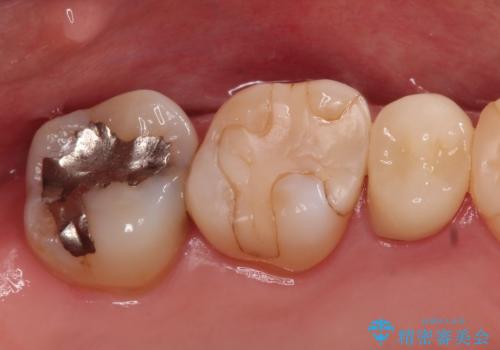

【セラミックインレー】虫歯の治療

- 虫歯を認めたため、セラミックインレーにて治療を行いました。

見た目も綺麗に修復することができ患者様には満足していただきました。

セラミックインレーの接着には必ずラバーダム防湿を行なっています。